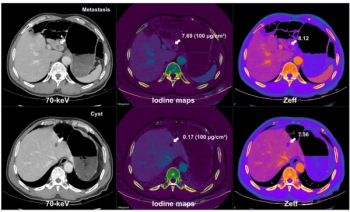

New research suggests the combination of multiparametric dual-energy CT and deep learning image reconstruction for liver metastases detection enables a 45 percent reduction in radiation dosing.